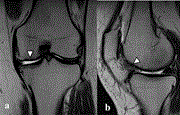

Plica syndrome after medial patellofemoral ligament reconstruction: a case report

Tomoya Iwaasa and others

Journal of Surgical Case Reports, Volume 2020, Issue 4, April 2020, rjaa036, https://doi.org/10.1093/jscr/rjaa036

Silent burn: the hidden danger and effects of bright light from fibre-optic cables in arthroscopic knee surgery

Jai Chitnavis

Journal of Surgical Case Reports, Volume 2020, Issue 4, April 2020, rjaa068, https://doi.org/10.1093/jscr/rjaa068